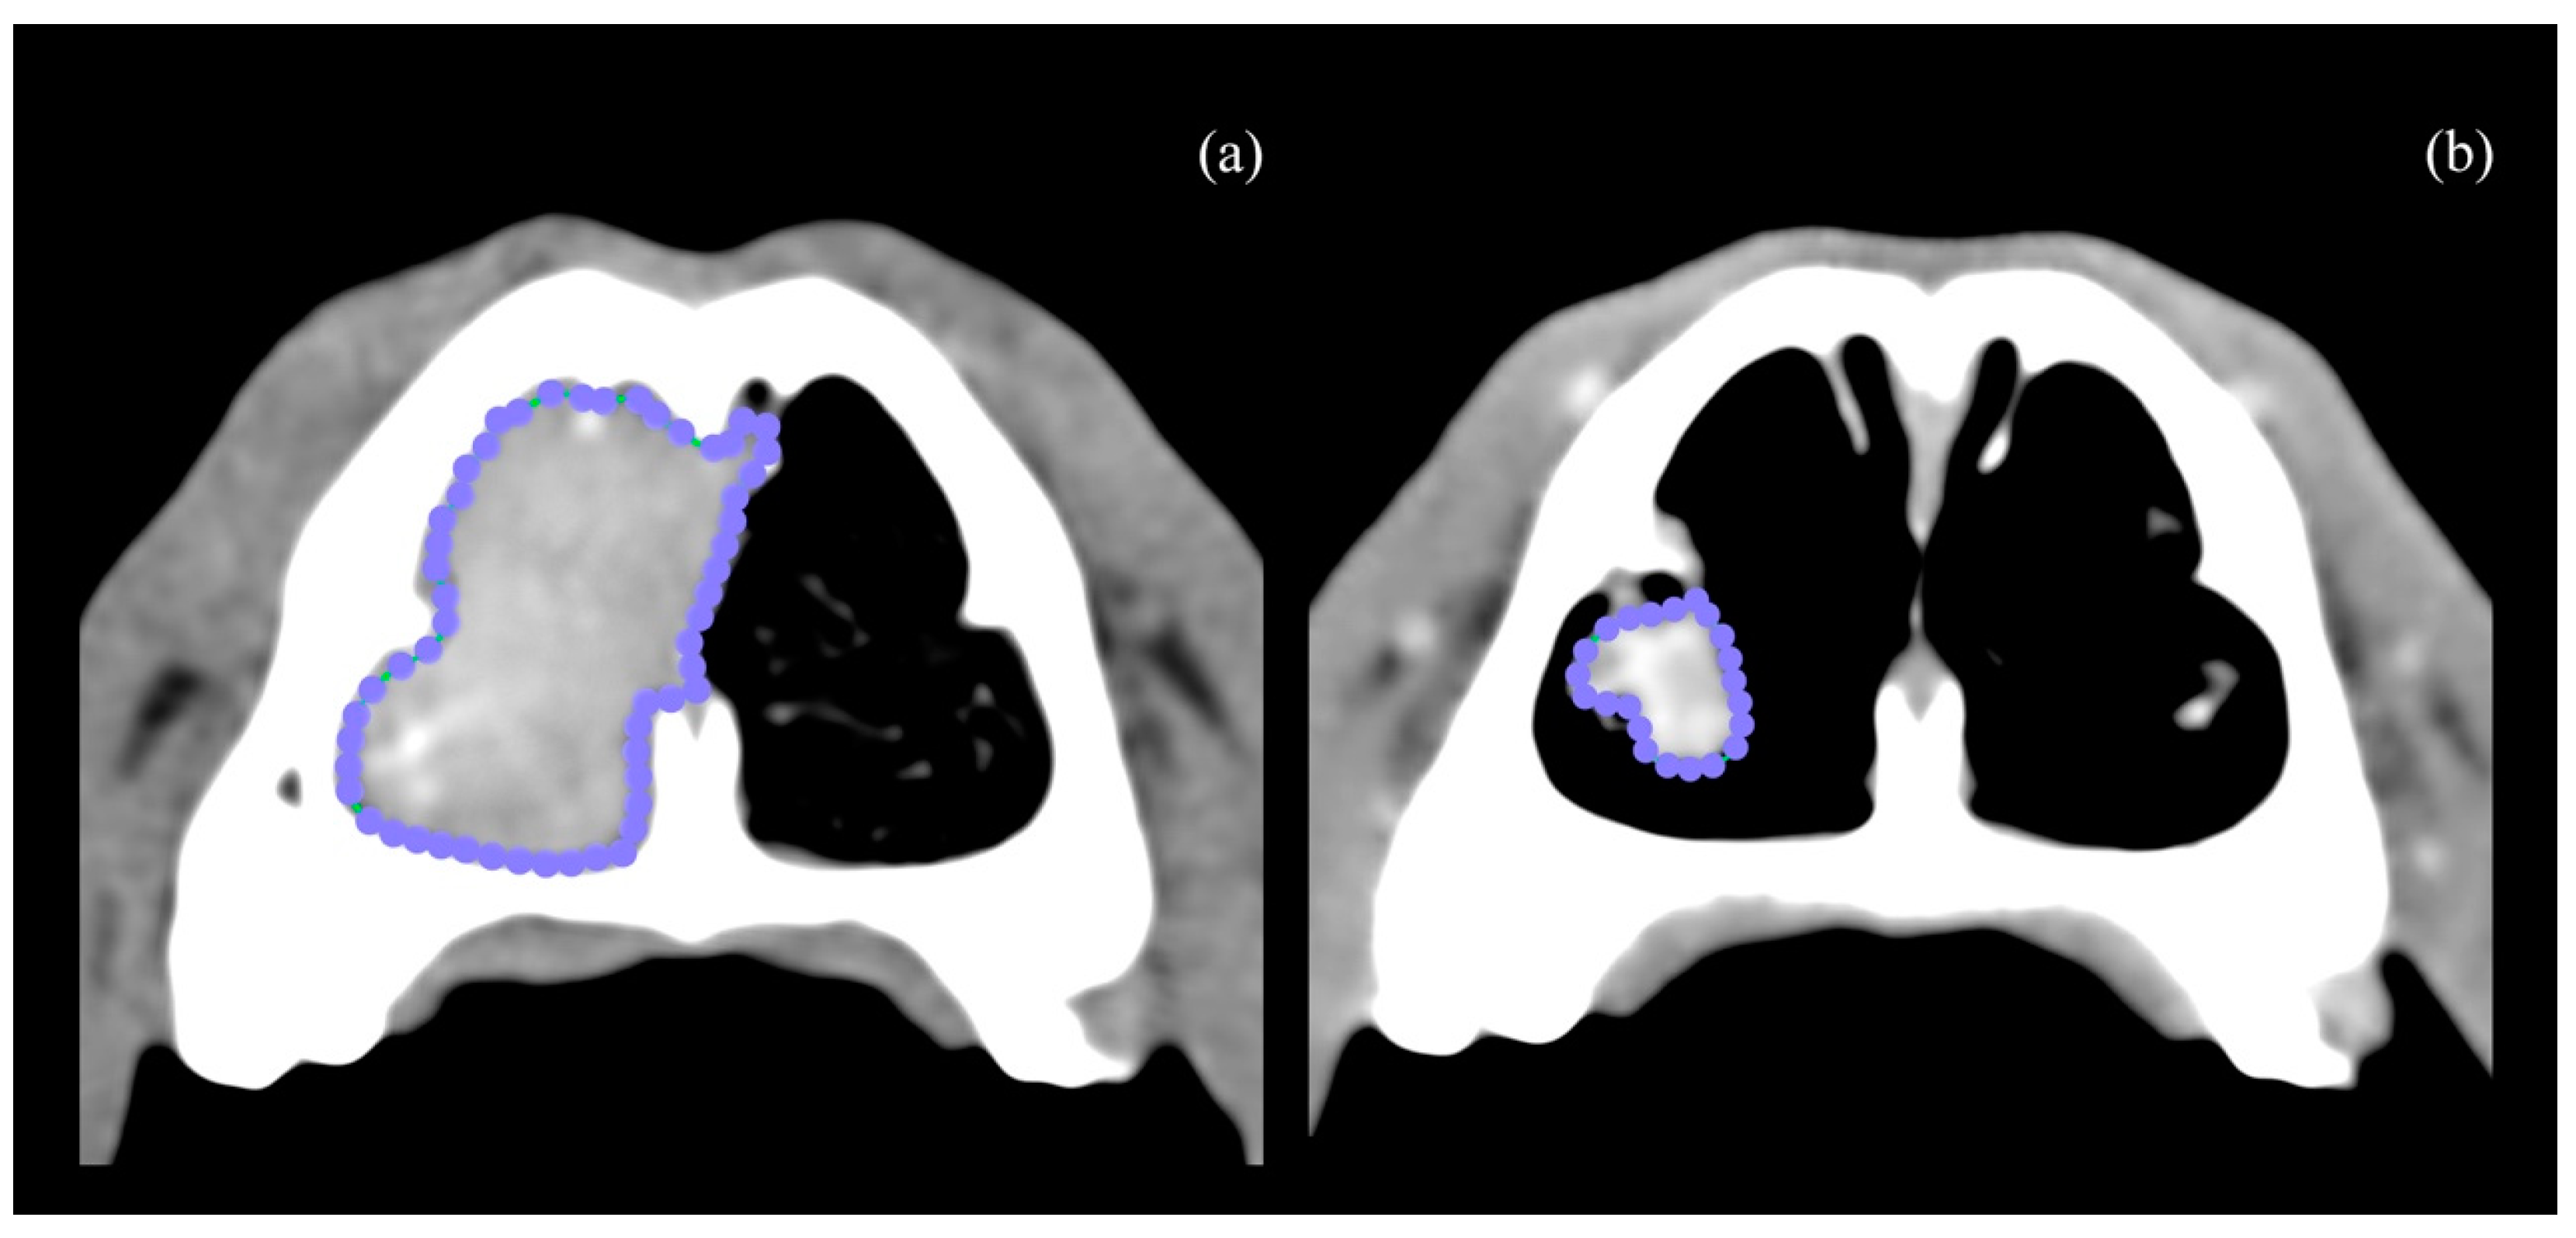

| Variable | Time | Mean | SD | min | Q1 | Q2 | Q3 | Max | p-Value w |

|---|---|---|---|---|---|---|---|---|---|

| HU | T0 | 98.2 | 6.6 | 87 | 95 | 98 | 101.5 | 110 | 0.001 |

| T1 | 60.9 | 9.4 | 50 | 52.5 | 61 | 67.5 | 78 | ||

| Attenuation reduction (%) | 37.6 | 11.1 | 11.4 | 32.4 | 38 | 46.1 | 51.8 | ||

| Volume (cm3) | T0 | 25.2 | 11.1 | 12.3 | 17.0 | 19.5 | 35.7 | 43.8 | 0.001 |

| T2 | 4.4 | 2.7 | 2.2 | 2.6 | 3.2 | 4.8 | 11.2 | ||

| Volume reduction (%) | 82.8 | 4.5 | 74.4 | 81.5 | 83.1 | 84.7 | 9.1 | ||